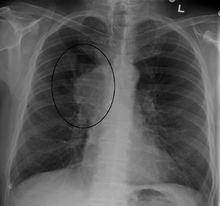

The main techniques of diagnosing SVCS are with chest X-rays (CXR), CT scans, transbronchial needle aspiration at bronchoscopy and mediastinoscopy.[3] CXRs provide the ability to show mediastinal widening and may show the presenting primary cause of SVCS.[3] CT scans should be contrast enhanced and be taken on the neck, chest, lower abdomen and pelvis.[3] They may also show the underlying cause and the extent to which the disease has progressed.[3]